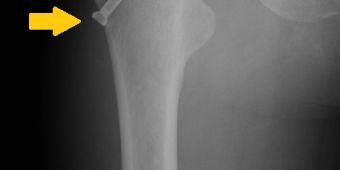

asnis1

Nach Anborung des Nekroseareals, Einbringen von gesundem Knochen und Implantation einer osteoinduktiven Spezialschraube (Pfeil). © Asklepios

Therapie: der erkrankte Knochen wird durch gesunden Knochen ersetzt

Die Hüftarthroskopie ermöglicht die Therapie von Gelenkveränderungen und die Beurteilung des Erkrankungsstadiums der Hüftkopfnekrose. Daraus ergibt sich eine gezielte stadiengerechte Therapie, die eine Erneuerung der Blutversorgung des Hüftkopfes und das Einbringen von gesundem Knochengewebe erfordert.

Dies gelingt mit speziellen Bohrern und Stößeln, die anhand von bildgestützten Verfahren gezielt in die erkrankten Knochenareale vordringen können, wobei gesundes Knochengewebe aus dem Beckenkamm oder dem Oberschenkelknochen in die erkrankten Knochenareale transplantiert und eingebracht werden. Je nach Erkrankungsstadium kann außerdem zusätzlich eine osteoinduktive Schraube (Asnis-Schraube; Bild) in das Knochengewebe eingebracht werden.